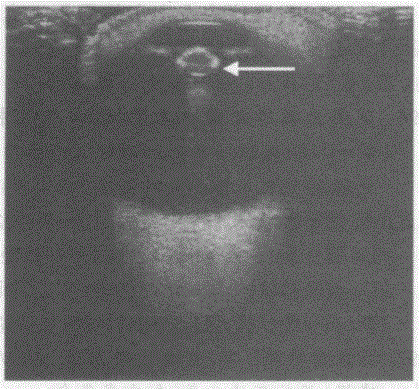

问题 临床资料:男,75岁,自述进行性视物模糊。 超声综合描述:眼球形态正常,晶状体前后皮质回声增强,内透声不清亮,呈椭圆形强回声(箭头所指)。 超声提示:

选项 A.人工晶状体植入 B.晶状体混浊(白内障) C.球内异物 D.玻璃体出血

答案 B